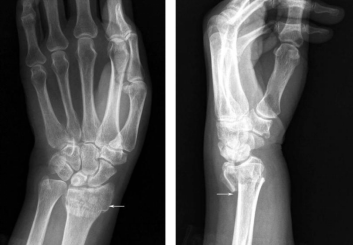

X线能清楚地拍出骨性结构(下图中白色轮廓清晰部分)但却不能清晰地分辨出软组织结构(边缘白色模糊部分)。因此,在常规摄片排除骨折表现后,患者通常会把受伤局部的肿胀、疼痛及运动障碍等不适,统称为伤筋,医学上则称为软组织损伤。

图1 手部X线片(白色部位为骨骼,边缘白色模糊部分为软组织)

图片来源:X线读片指南——王书轩、范国光主编